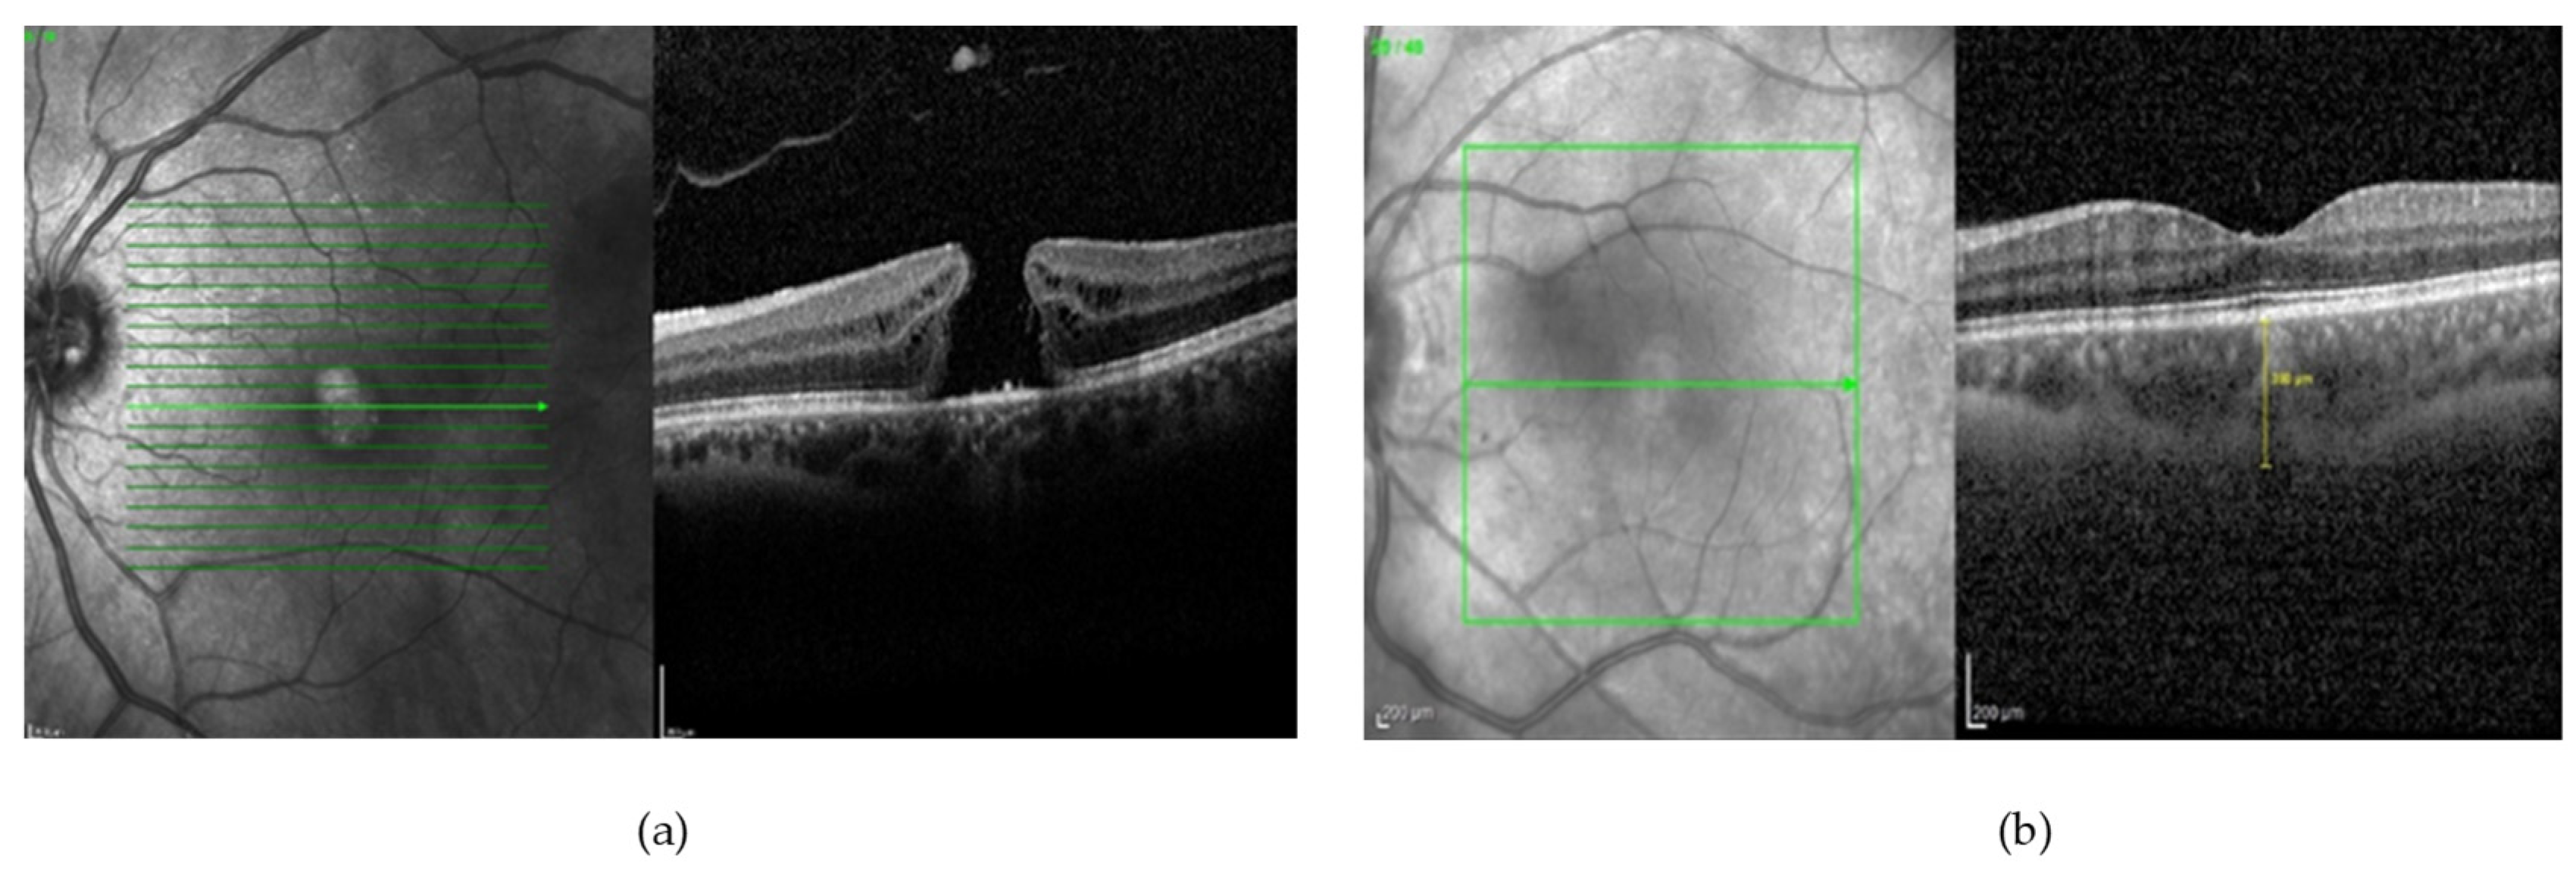

- Wu, M.; Chen, Q.; He, X.J.; Li, P.; Fan, W.; Yuan, S.T.; Park, H. Automatic Subretinal Fluid Segmentation of Retinal SD-OCT Images with Neurosensory Retinal Detachment Guided by Enface Fundus Imaging. IEEE Trans. Biomed. Eng. 2018, 65, 87–95. [Google Scholar] [CrossRef]